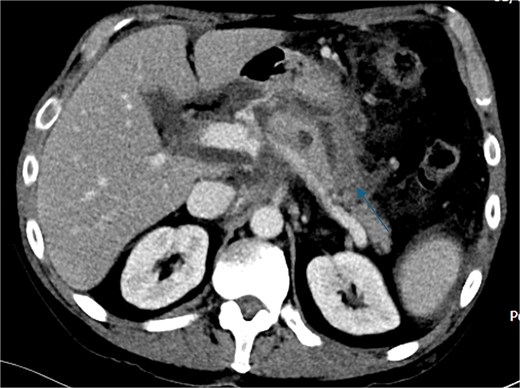

Despite the absence of abdominal symptoms, a computed tomography of the abdomen and pelvis (CTAP) was performed due to markedly elevated lipase levels. The CTAP (Figs 3–5) revealed evidence of acute pancreatitis (Fig. 5, arrow), with a complex peripancreatic fluid collection (Fig. 3, arrow). Additionally, a focal thrombus was observed within the portal venous confluence (Fig. 4, arrow). Further ultrasound of the gallbladder was negative for gallstones (Fig. 6), ruling out gallstone-induced pancreatitis.

Recovery was complicated by progressive necrotising pancreatitis with evidence of active bleeding into a peripancreatic collection (Fig. 7) and a pseudoaneurysm arising from a branch of the superior mesenteric artery (SMA) associated with haemoperitoneum (Fig. 8).

CT angiogram of abdomen axial view; contrast extravasation, indicating active bleeding within this peripancreatic collection.